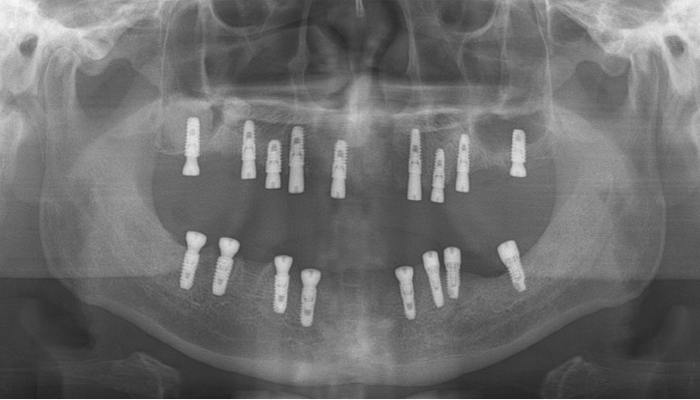

• 식립전

식립후